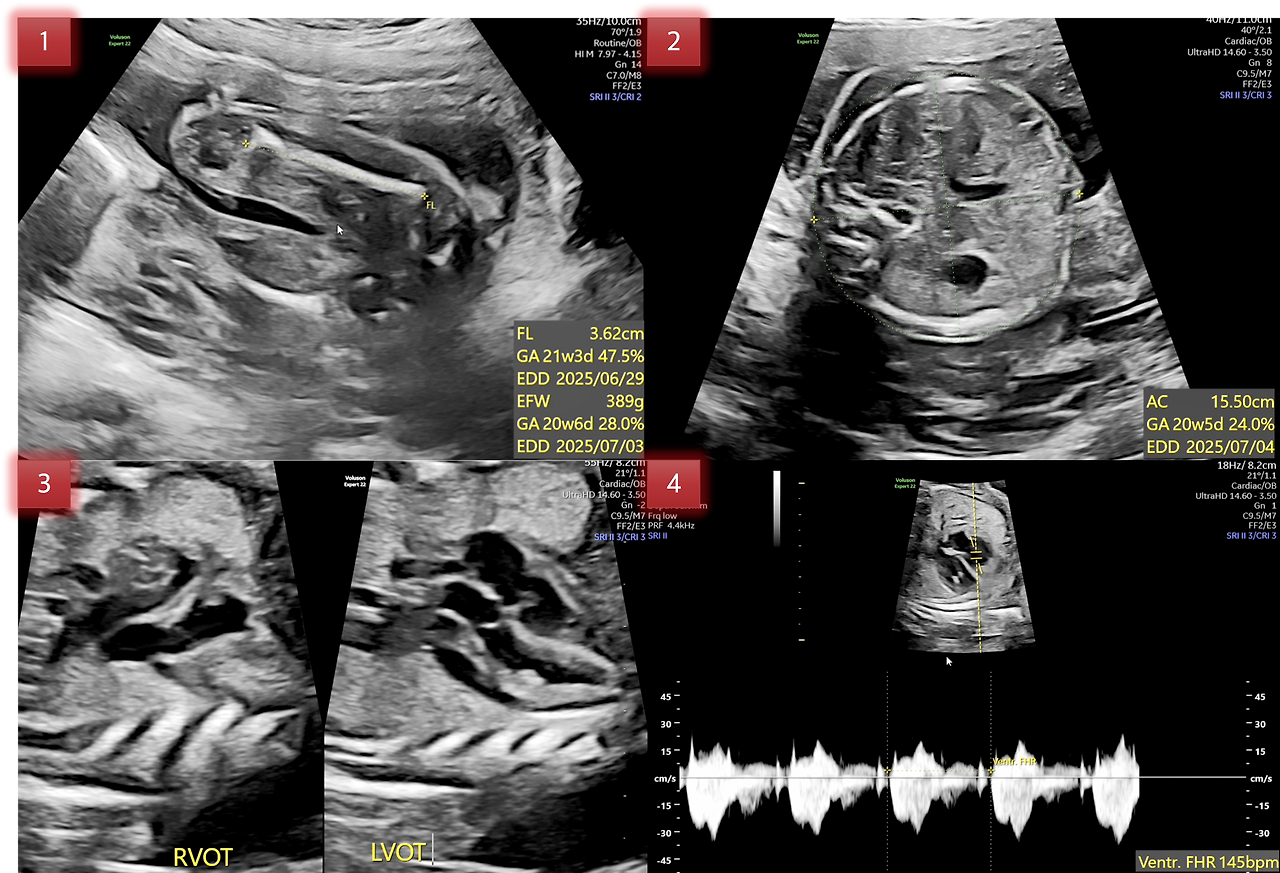

아래 1번 사진은 FL(Femur Length)로 허벅지 뼈의 길이이고, 다리 전체 길이가 아닙니다. 그리고 아래에 EFW(Estimated Fetal Weight)가 있는데 태아 추정 체중을 말합니다.

현재 추정 체중은 289g으로 임신 20주 차 정도에 해당됩니다.

2번 사진은 AC(Abdominal Circumference)로 태아의 복부 둘레를 말하는데요. 보통 허리둘레를 재는 것처럼 배의 단면의 둘레를 측정합니다.

3번은 좌심실 유출로(LVOT), 우심실 유출로(RVOT)를 확인한 사진인데 아마 심실 결손과 관련된 이상부위를 확인하는 목적인 듯합니다.

4번은 심장박동수를 측정한 사진인데, 145 bpm으로 임신 21주~25주 평균과 동일하네요. 임신 주수가 늘어날수록 심장박동수는 줄어든다고 하네요.